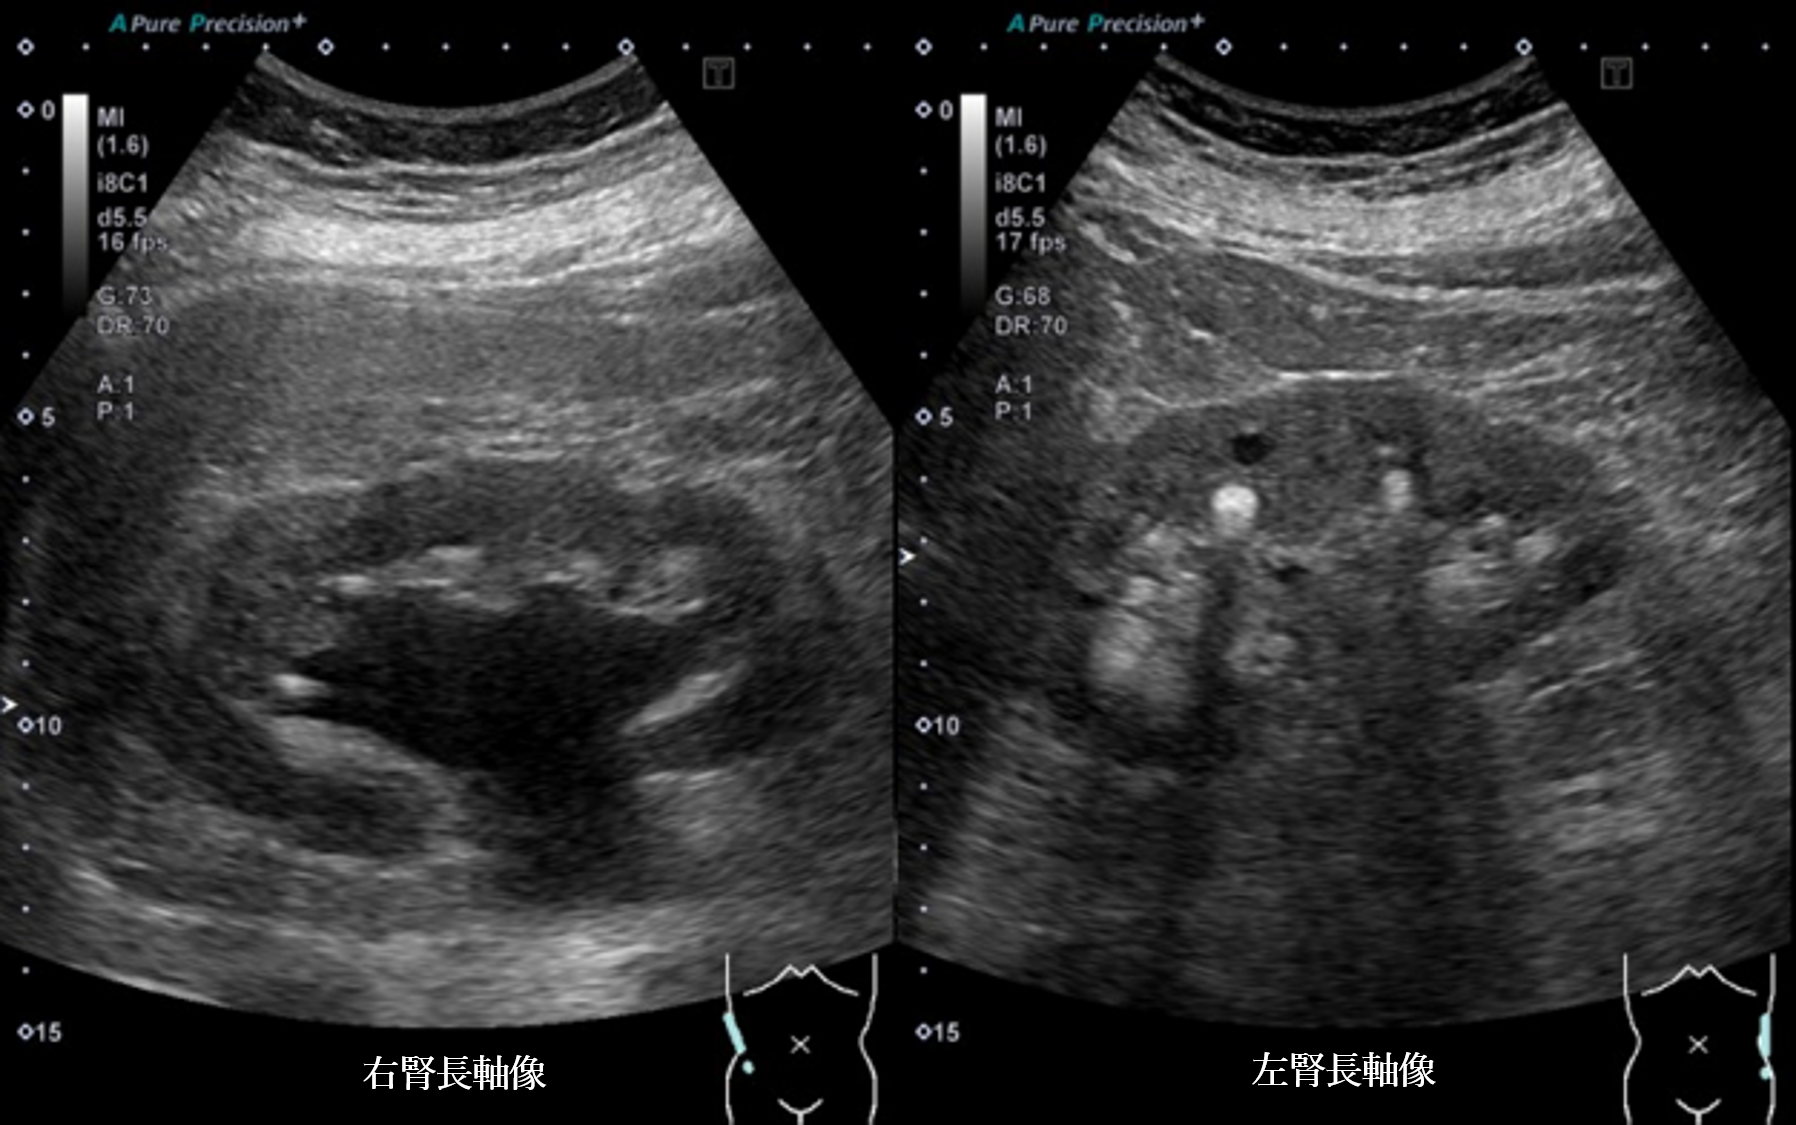

腹部超音波2 動画1 右腎長軸像(No18-19_A)

腹部超音波2 動画1(No18-19_A)

腹部超音波2 動画2 左腎長軸像(No18-19_B)

腹部超音波2 動画2(No18.19_B)

② 両腎内に strong echo 像を多数認める

③ 左腎に明らかな腎盂腎杯拡張は認めない

④ 右腎の腎盂拡張および右尿管拡張を認める

⑤ 右腎中心部エコー内に無エコー領域を認める